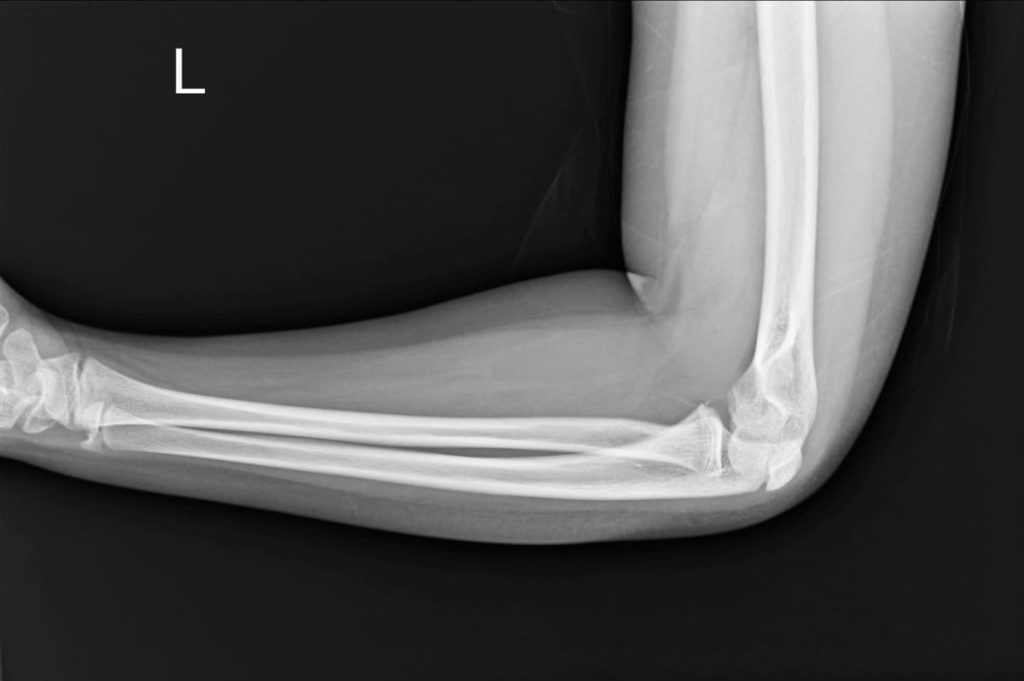

radiographie du coude

Surgical Treatment of Ulnar Nerve Compression at the Elbow

Overview of surgical approaches to treat ulnar nerve compression and restore upper limb function.